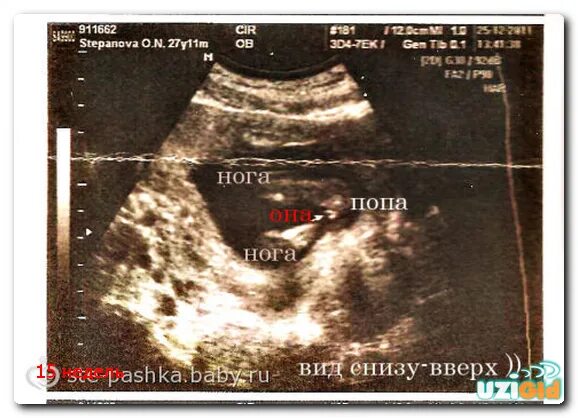

15 неделя можно узнать пол ребенка